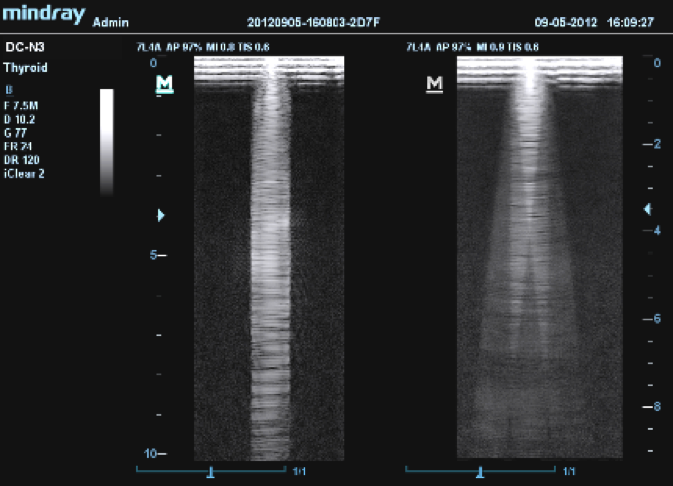

Данная технология представлена практически у каждого производителя ультразвуковой диагностической медицинской техники. У компании GE, данная технология поставляется под наименованием CrossBeam, у Mindray – iBeam, Siemens – Advanced SieClear, Philips – SonoCT, Esaote – Mview и т.д. Как и в случае с множеством других технологий, применяемых в ультразвуковом аппарате, здесь мы также имеем дело с одной и тойже технологией компаундинга. Различия в названиях на 99% - маркетинговый ход, и на 1% отличия для возможности запатентовать именно свою, брендованную технологию компаундинга (здесь стоит пояснить, что это сугубо наше мнение).

На практике, применение технологии многолучевого составного сканирования (компаундинга) давно стало стандартом. Сегодня, практически все производители включают данный режим в базовый комплект поставки прибора, а причина этого очень проста – это именно та технология, которая позволяет нам значительно уменьшить акустические тени и увеличить контрастное разрешение.

Принцип работы многолучевого составного сканирования (компаундинга) заключается в объединении кадров, полученных при генерации ультразвука под разными углами.

Предлагаем вам ознакомиться с примером применения данной технологии. Изображения выполнены на приборе Mindray DC-8, на верхнем изображении режим iBeam (компаундинг) отключен, а на нижнем включен на первую ступень регулировки (3 луча).